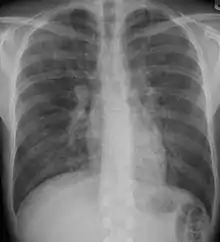

X-rays

Chest radiography is usually the first test to detect interstitial lung diseases, but the chest radiograph can be normal in up to 10% of patients, especially early in the disease process.[12][13]

High resolution CT of the chest is the preferred modality, and differs from routine CT of the chest. Conventional (regular) CT chest examines 7–10 mm slices obtained at 10 mm intervals; high resolution CT examines 1–1.5 mm slices at 10 mm intervals using a high spatial frequency reconstruction algorithm. The HRCT therefore provides approximately 10 times more resolution than the conventional CT chest, allowing the HRCT to elicit details that cannot otherwise be visualized.[12][14]

Radiologic appearance alone however is not adequate and should be interpreted in the clinical context, keeping in mind the temporal profile of the disease process.[12]